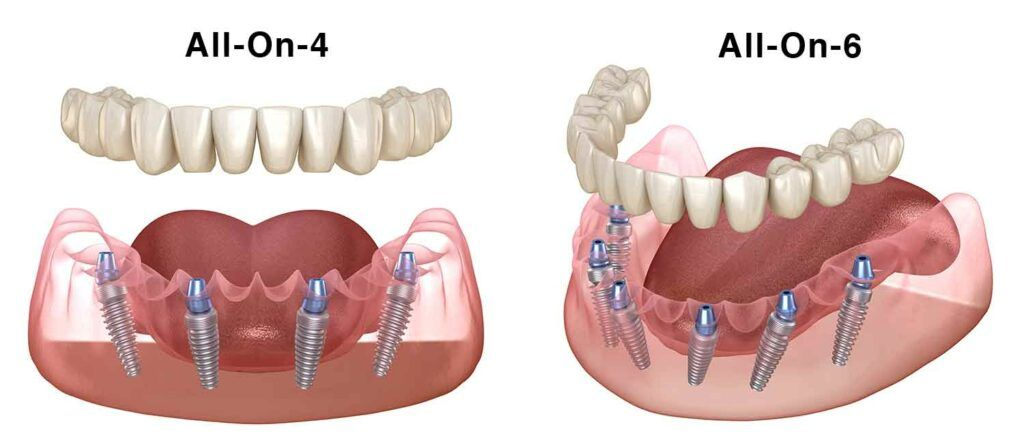

Missing teeth can be stressful, but with modern full-mouth implant, you can easily get your smile back! Two popular options are All-on-4 and All-on-6 implants. Wondering which one is right for you? Let’s break it down! Quick Summary What Are Full Mouth Implants? What...